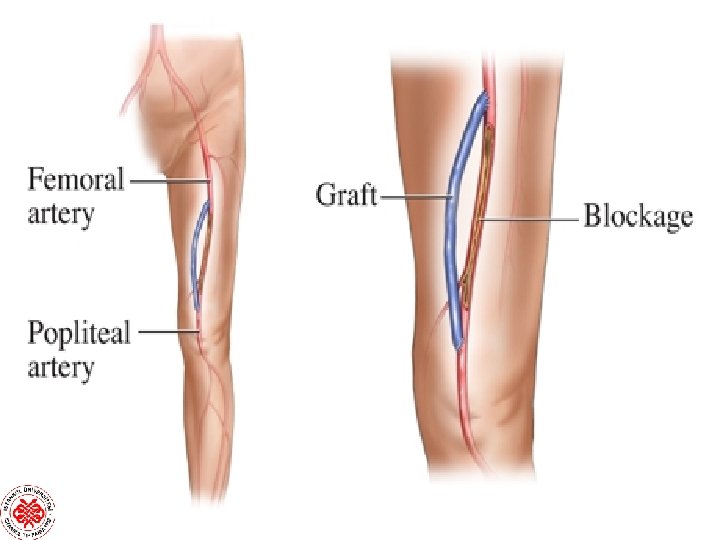

SAFEN GREFT